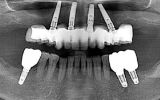

オールオン4の患者さま

オールオン4(All-on-4)は、1998年にDr.パウロ・マロが臨床研究チームとともに開発した画期的な治療法です。顎骨にインプラントを傾斜させて埋め込むことで、最少本数の4本(日本人の場合は上顎が5~6本になることも)で全ての人工歯を支えることができます。そのため、歯のほとんどが噛めない方に最適で噛む喜びや美しい歯の喜びをご提供します。

- 施術の説明インプラントを傾斜させて埋め込むことで、最少本数の4本(日本人の上顎の場合は5~6本で支えることもあります)で、全ての人工歯を支えることができる施術。